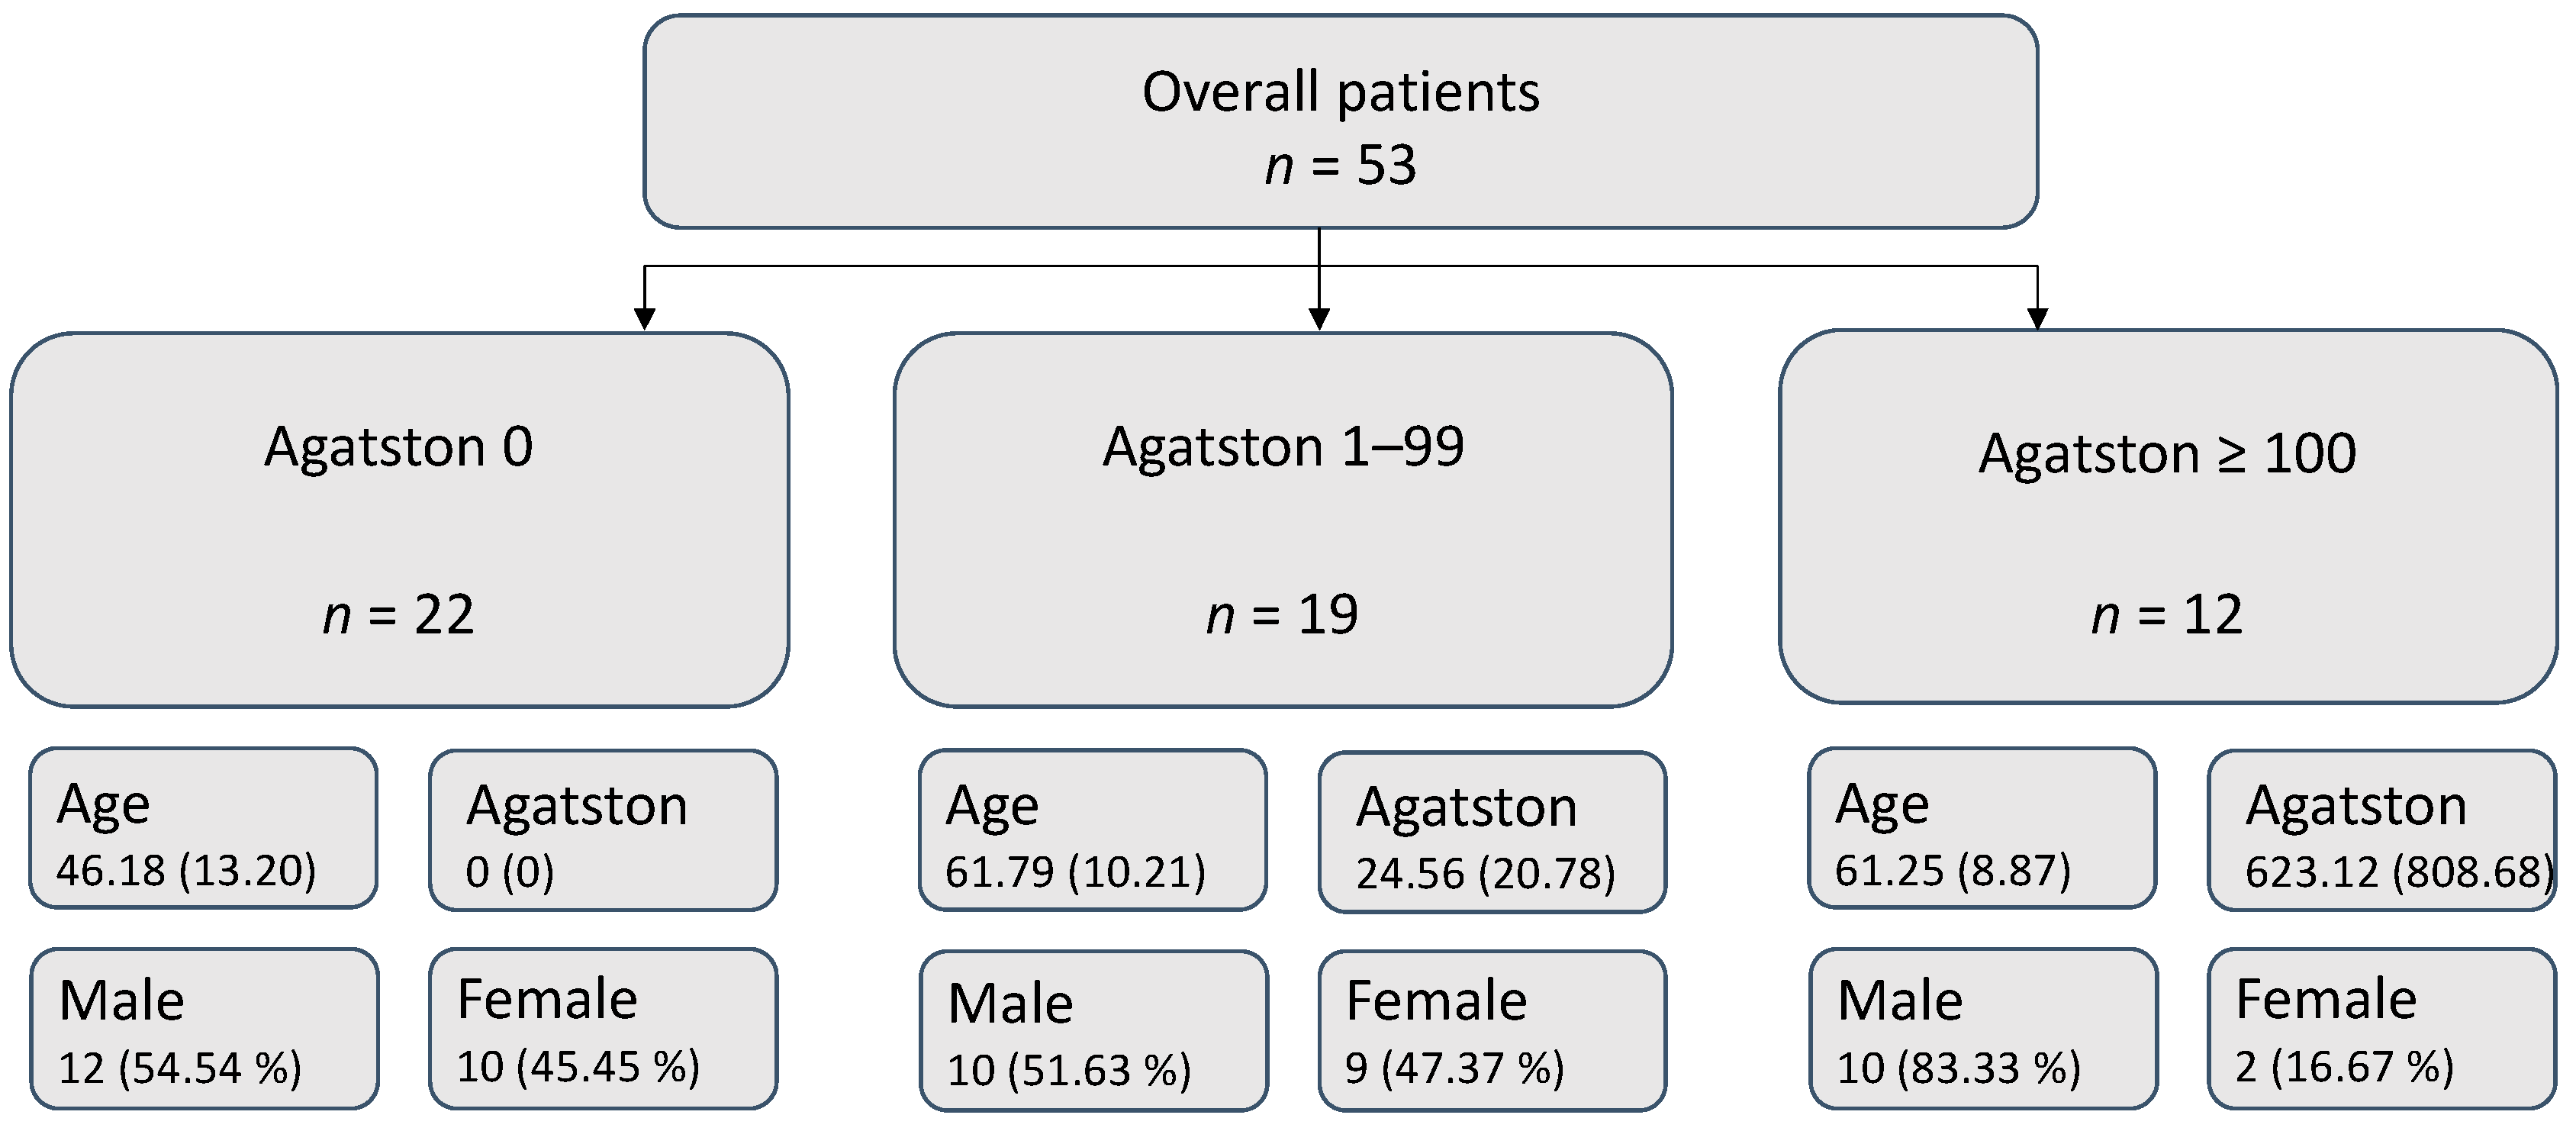

3.1. Patient Collective

3.2. Cluster Analysis